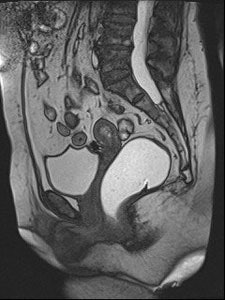

Sagittal late evacuation view shows a cystocele in the middle and posterior pelvic floor compartment. Image courtesy of Dr. Steve Halligan.